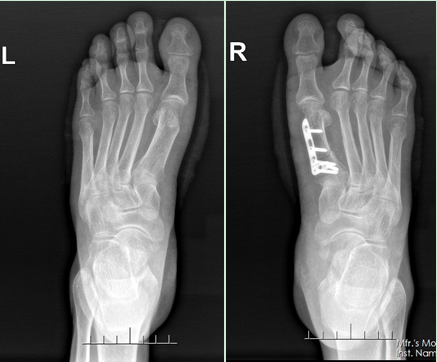

患者脚趾严重畸形。

患者手术后踇外翻得到有效纠正。李兰(化名)从20来岁开始就喜欢穿高跟鞋,如今57岁的她鞋柜里还保留着不少高跟鞋和尖头鞋。大概10年前,李兰发现自己的脚底板经常痛,大脚趾有点往里歪,按上去还有点儿疼痛。近年来,她发现自己大脚趾头歪得越来越。上个月初,李兰的脚更是痛得连路都走不了。“即使是穿平底鞋,走十几米不到就得停下来歇息。”痛苦不堪的她找到了广东三九脑科医院骨科主任柴亚胜。

柴亚胜接诊时发现,患者左脚大拇指往其他趾头的方向弯了近30°,而右脚就更加严重了,外翻角度将近40°,严重挤压了第二趾和第三趾。柴亚胜说,这是典型的“踇外翻畸形”,大多数人发病的原因跟常年穿高跟鞋、尖头鞋有重要关系。不过像李兰这样的情况就比较严重,需进行截骨矫形手术才能恢复正常走路。

完善相关检查后,柴亚胜为患者实施了“左脚第一跖骨头截骨、踇外翻矫形术和右脚第一跖骨截骨矫形内固定、踇外翻矫形术”。术中,患者左右脚的踇外翻得到有效纠正,术后疼痛症状减轻,术后一周便可以穿减压鞋下床走路。